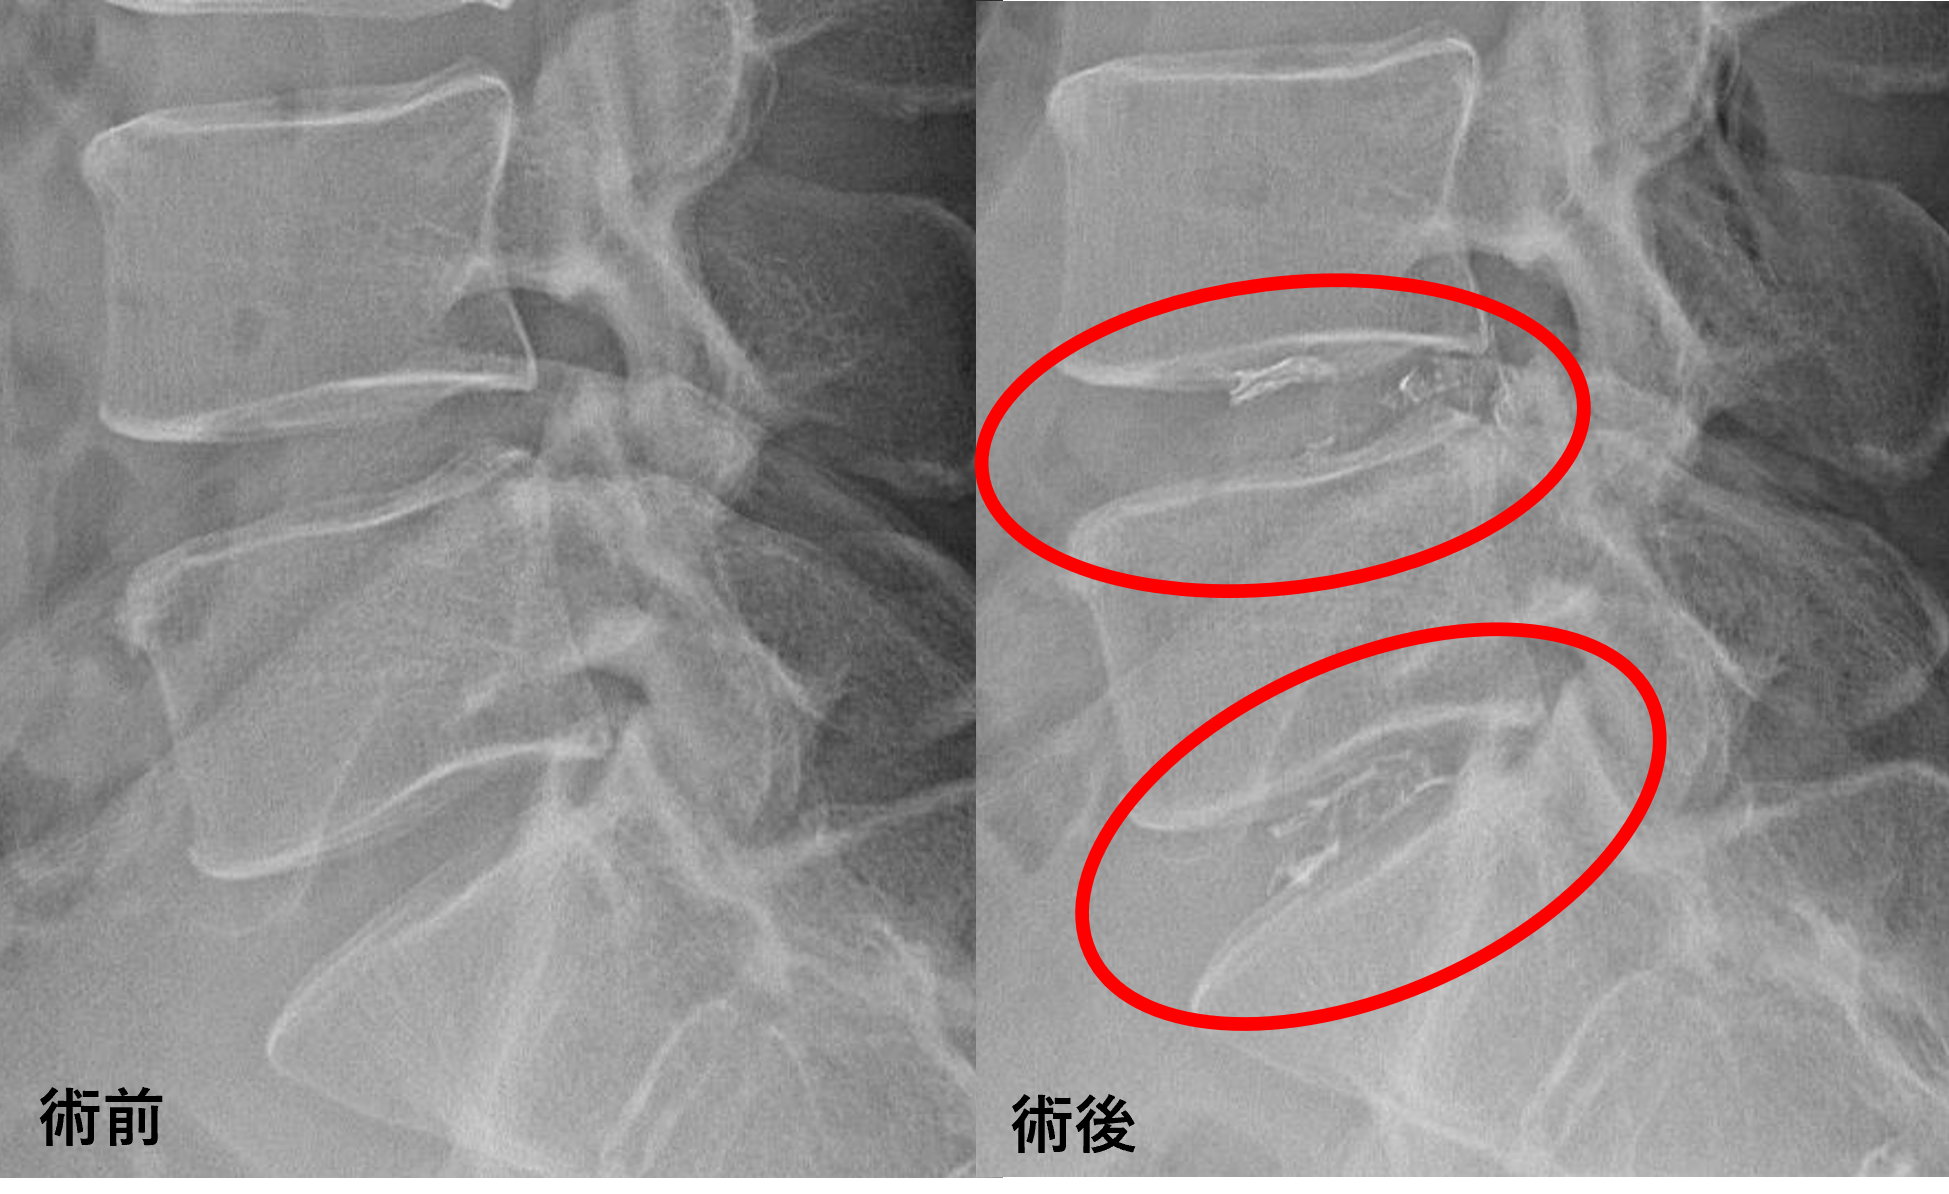

- L4/5、5/s – 椎間板変性、膨隆

以上のことが画像上認められました。

L4/5、5/sの椎間板所見による脊柱管の圧排が、症状の原因の可能性が高い。

患者様と相談の元、L4/5、5/sにセルゲル法を施行

※この患者様のケースの費用:セルゲル2箇所=1,430,000円(税込み)